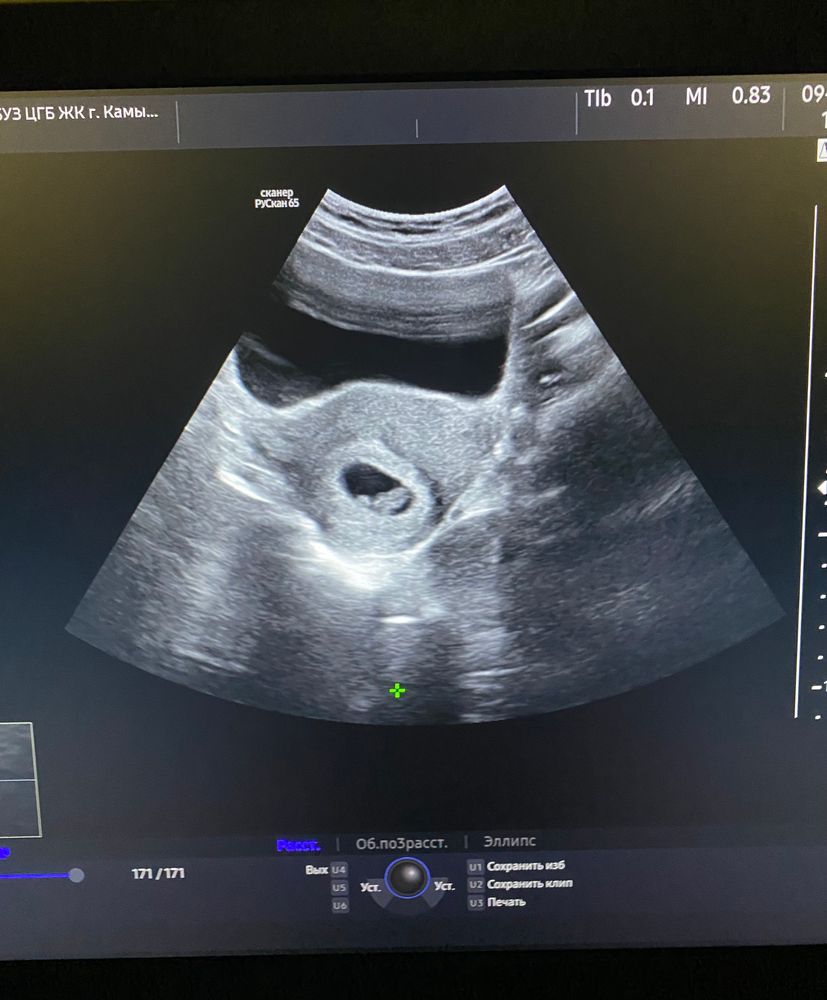

УЗИ, очень переживаю

Девочки всем привет, ничего не понимаю, подскажите пожалуйста, ходила вчера на узи, ктр 2мм, ставят срок 4-5 недель, хотя последние м были 22.09.23, то есть срок то уже больше, сердечко не услышали еще, 1 числа снова на узи, очень переживаю

1 ноября делали узи, ставили срок 4 недели, потом была кровь, побежала опять на узи 6 ноября, стави